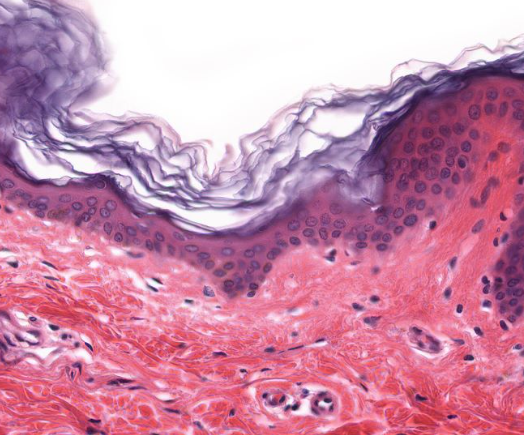

Keratinized Stratified Squamous Epithelial Tissue